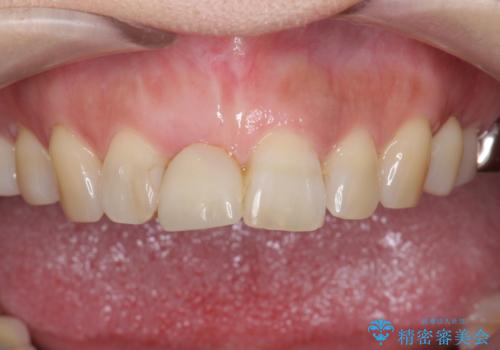

- 前歯を外傷により失い、審美性の改善を求めて来院されました。

横の歯を削る必要のあるブリッジ治療、着脱の必要な入れ歯に強い抵抗があったためインプラント治療を計画します。

前歯のインプラントを審美的に仕上げるには、インプラント周囲に十分な骨の量と厚みのある歯肉、そして埋入位置の精密な位置付けが重要です。